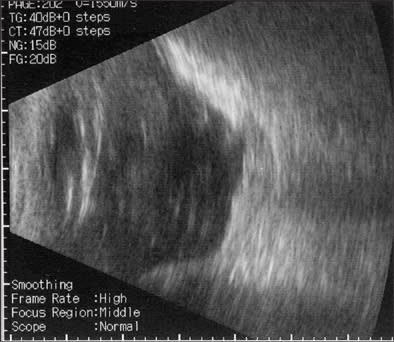

On postoperative day 2, the retinal lesions showed demarcation, suggesting regression of the active process (Figures 4 and 5). Her vision in OD had now declined to 20/600. Keratic precipitates were noted to regress in size and number. The retinal lesions continued to decrease over the course of the 10 days with a concomitant improvement of her vision to 20/400, so that we were comfortable to discharge the patient on oral acyclovir 800 mg 5 times per day. Acyclovir therapy was maintained over a total of 3 months. At 6 months postoperatively, we opted to remove the silicone oil during cataract surgery on her right eye. Subsequently, ocular hypotony developed in OD with choroidal detachments (Figure 6), which required a silicone oil refill. An aspirate from the vitreous cavity obtained during the latter procedure was again positive for V. zoster immunoglobulin A by immunofluorescence assay, which prompted us to resume oral acyclovir therapy with 400 mg 3 times per day, along with 8 mg prednisone po and prednisone ointment twice per day for her right eye.

|

| Figure 6. Ultrasound images showing detachment of ciliary body (left) and choroid (right) due to ocular hypotension. | |